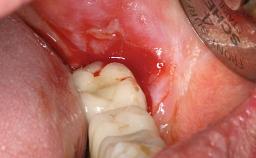

A 30-year-old female patient was referred to the Department of Periodontology of the University of Bern, Switzerland, by a dentist in private practice. Tooth 45 had been congenitally missing and had been replaced with a titanium implant three years prior to the first visit at the Department of Periodontology. The tissue level implant had a diameter of 4.1 mm, a length of 12 mm, and a sandblasted and acid-etched (SLA) surface (Straumann® Dental Implant System; Institut Straumann AG, Basel, Switzerland). The metal-ceramic crown on implant 45 had been cemented permanently. Implant 45 had been diagnosed with peri-implantitis by the referring dentist in the course of regular supportive care.